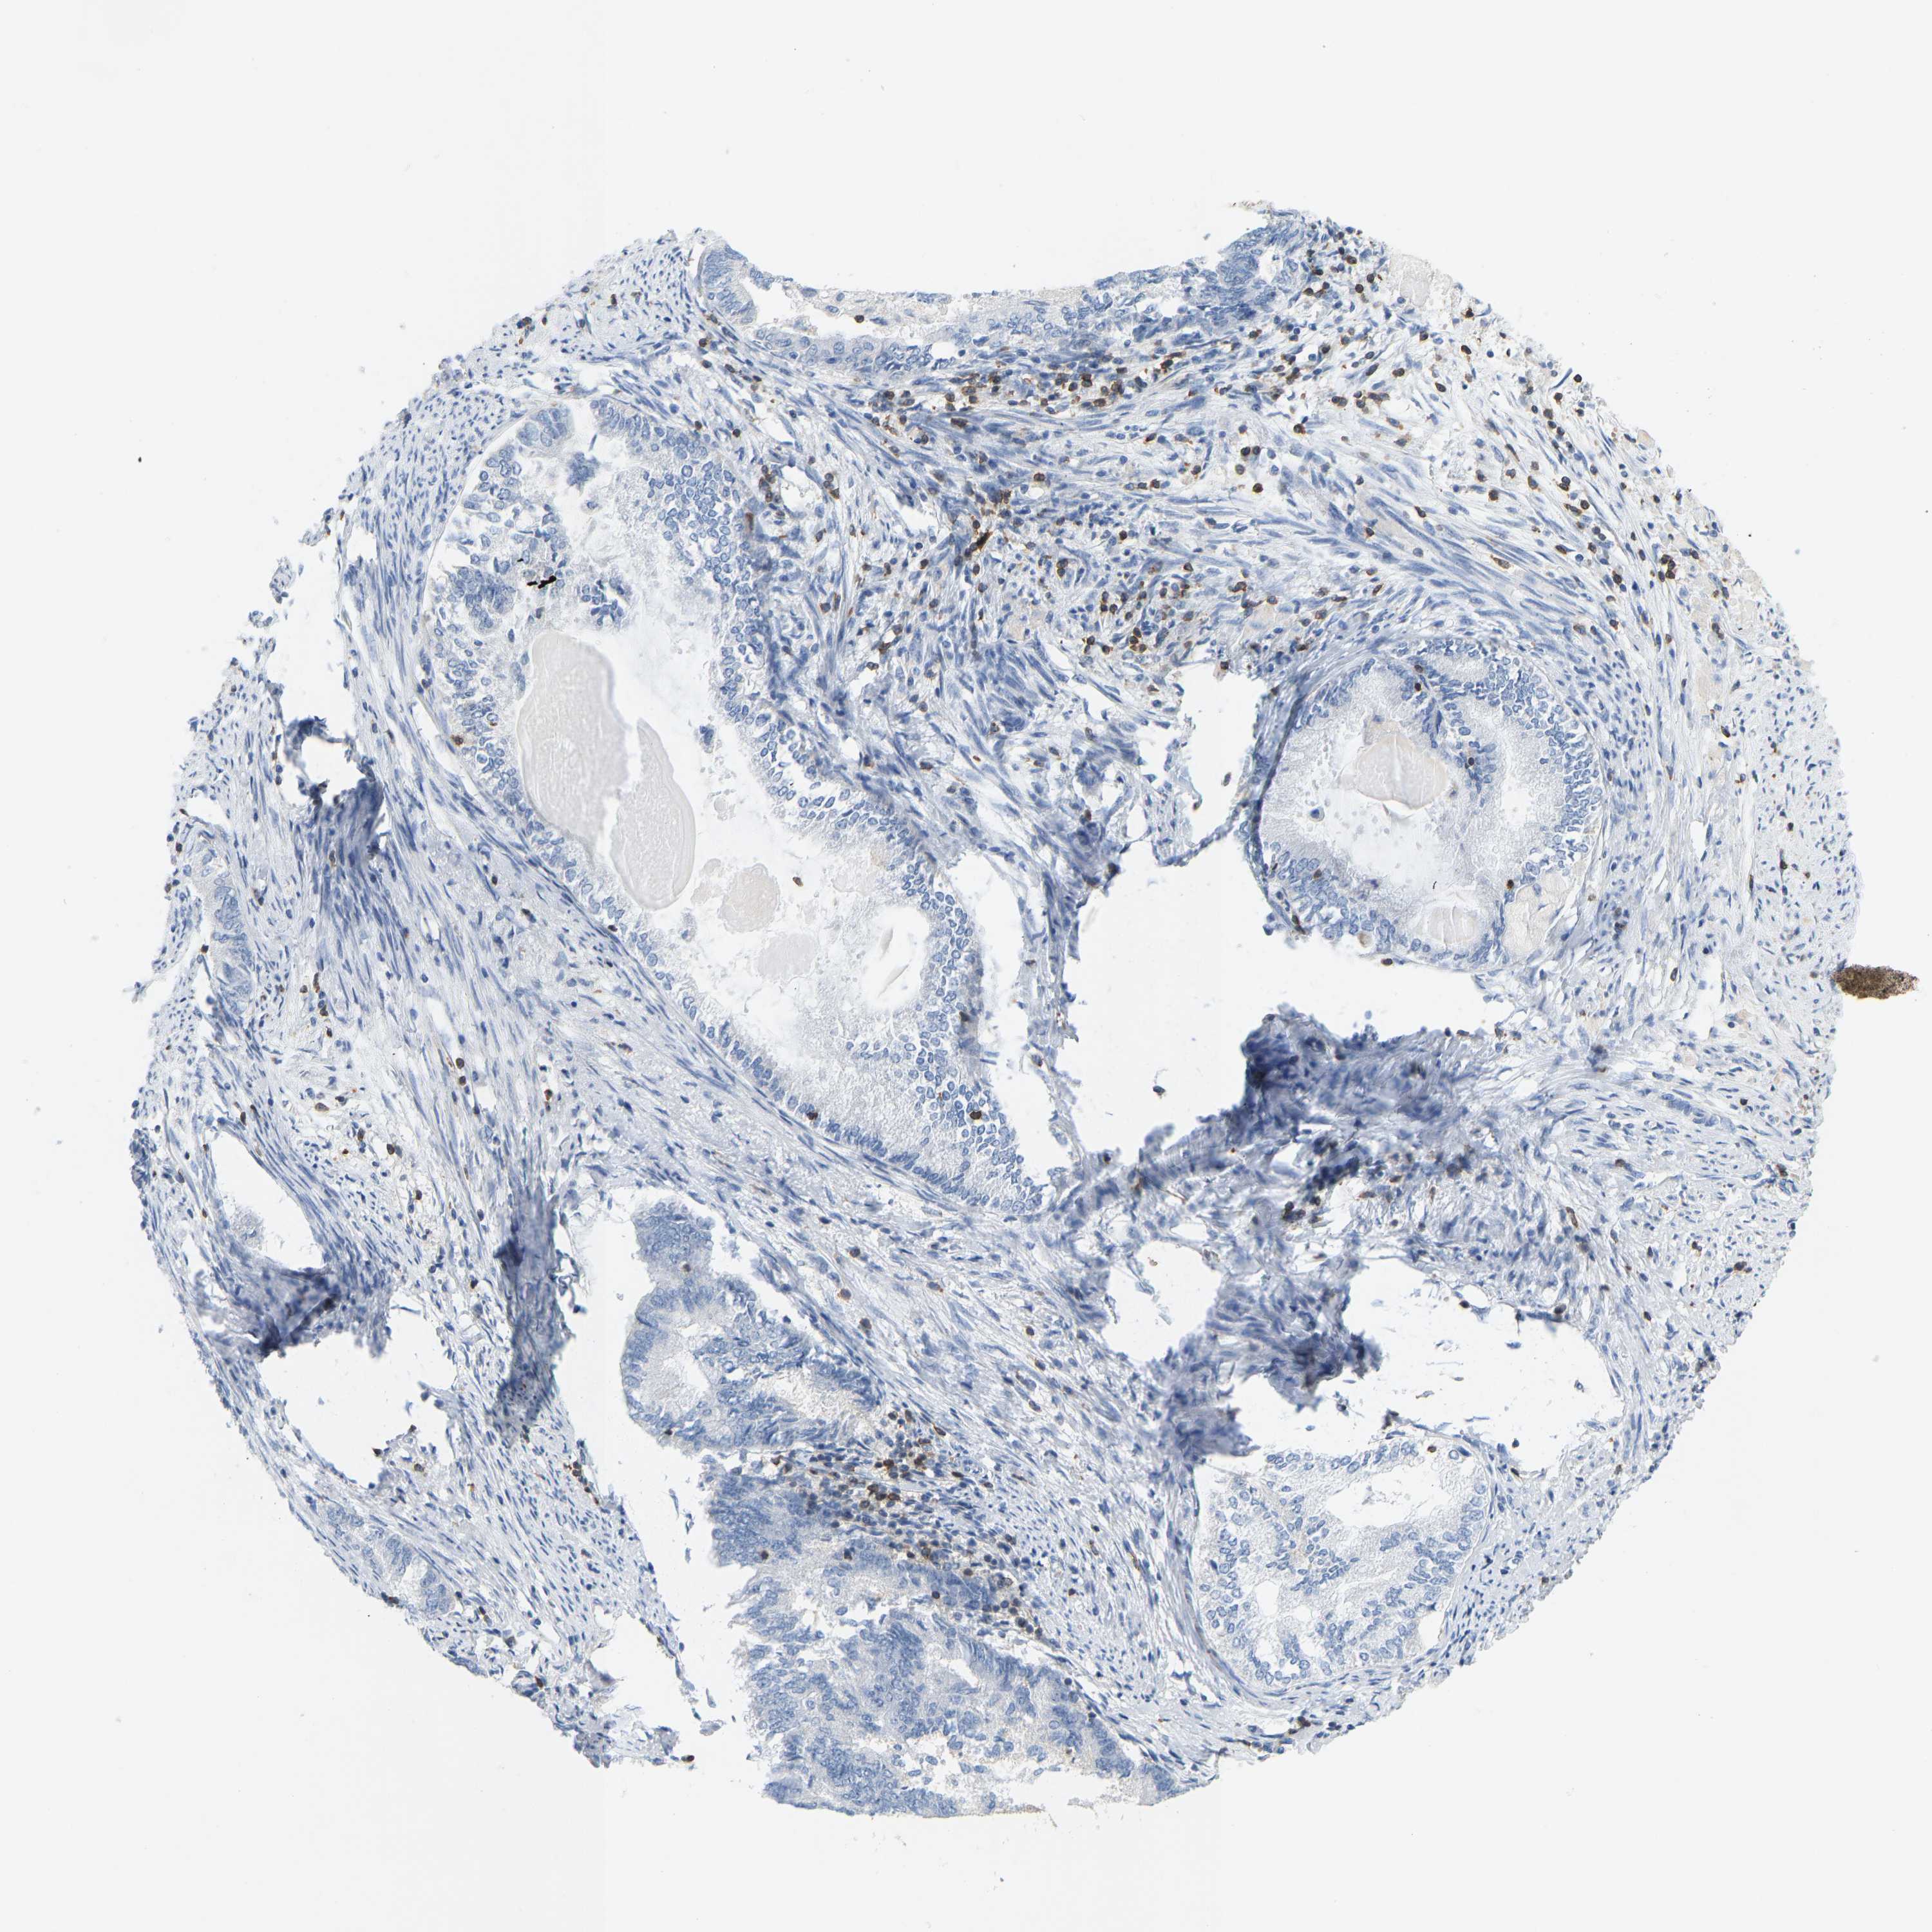

ENDOMETRIAL CANCER - Protein expressioni

A mouse-over function shows sample information and annotation data. Click on an image to view it in a full screen mode. Samples can be filtered based on level of antibody staining by selecting one or several of the following categories: high, medium, low and not detected. The assay and annotation is described here.

Note that samples used for immunohistochemistry by the Human Protein Atlas do not correspond to samples in the TCGA dataset.

Antibody stainingi

Antibody staining in the annotated cell types in the current human tissue is reported as not detected, low, medium, or high, based on conventional immunohistochemistry profiling in selected tissues. This score is based on the combination of the staining intensity and fraction of stained cells.

Each image is clickable and will lead to virtual microscopy that enables deeper exploration of all samples and also displays staining intensity scores, fraction scores and subcellular localization as well as patient and tissue information for each sample.

Antibody HPA018849

Antibody HPA019536

Antibody CAB033987

Staining

High

Medium

Low

Not detected

Intensity

Strong

Moderate

Weak

Negative

Quantity

>75%

75%-25%

<25%

None

Location

Nuclear

Cytoplasmic/membranous

Cytoplasmic/membranous,nuclear

Adenocarcinoma, NOS

Adenoma, NOS

Adenocarcinoma, metastatic, NOS